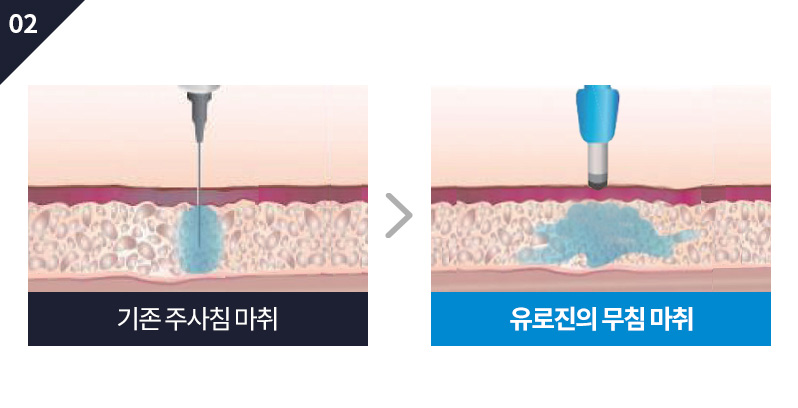

S Y S T E M

“ 차별화된 시스템을 통해 안정적이고 자연스러운

결과를 얻을 수 있도록 도움을 드리고 있습니다 ”

S E C R E T

“ 남성의 개인프라이버시 보호를 위해

시크릿 시스템을 진행합니다 ”